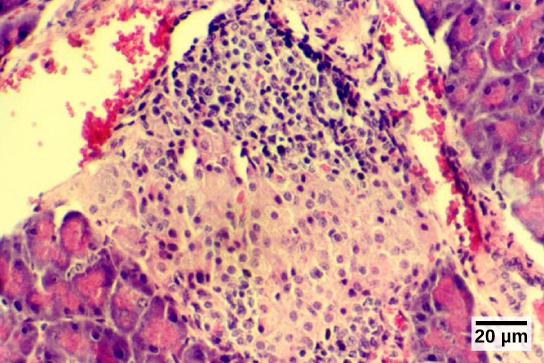

The gonads—the male testes and female ovaries—produce steroid hormones. The testes produce androgens, testosterone being the most prominent, which allow for the development of secondary sex characteristics and the production of sperm cells. The ovaries produce estradiol and progesterone, which cause secondary sex characteristics and prepare the body for childbirth.